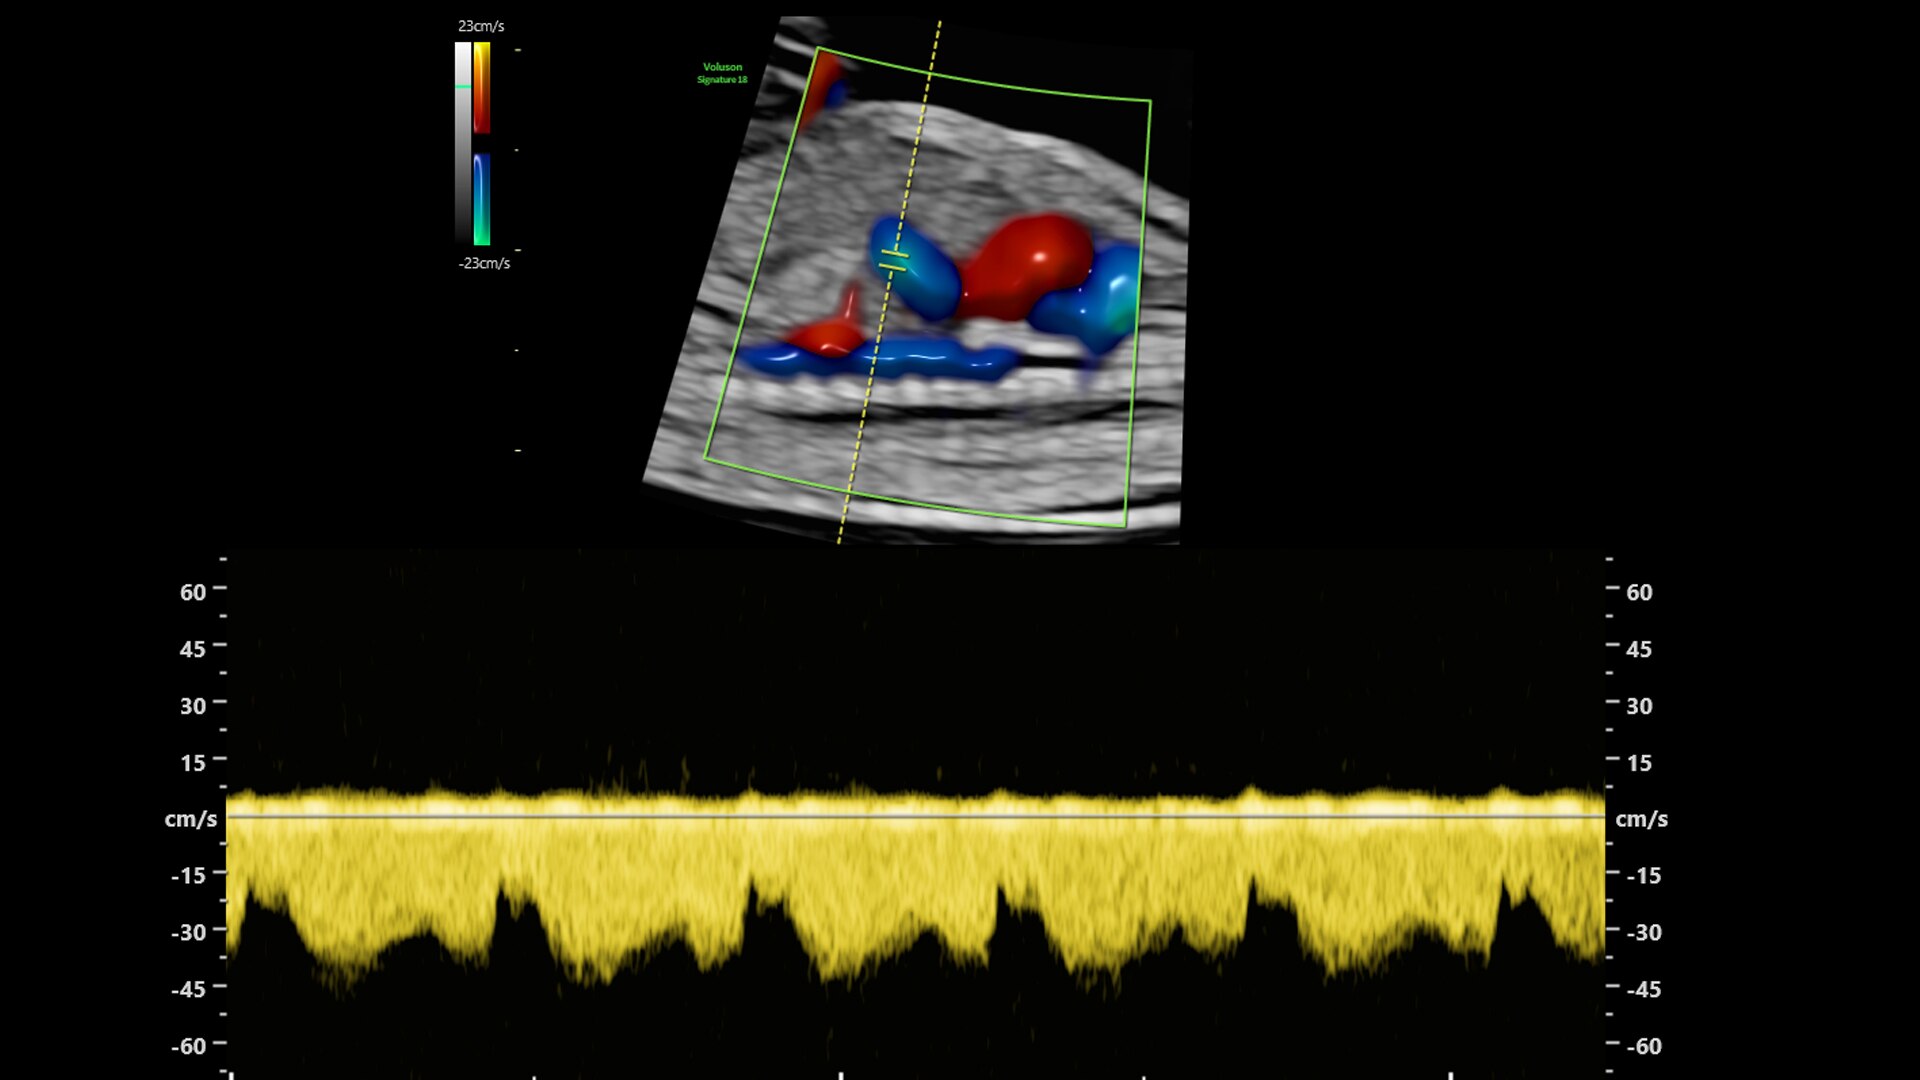

Flow Profiles

Reduce exam time by 56% with Flow Profiles. Dramatically simplifies color and pulsed-wave Doppler optimization by utilizing predefined and optimized settings.